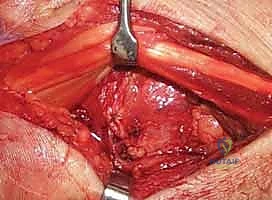

Surgeon: "Now that the dorsal capsule is visible, we need to gain access to the carpus. We'll make a capsular incision. Often, in these high-energy injuries, you'll find a transverse rent already present through the dorsal capsule and radiotriquetral ligament. We'll extend this rent carefully in both radial and ulnar directions to allow full visualization of the capitolunate interval and the entire carpus."

- Alternative Capsular Incision (Ligament-Sparing):

Surgeon: "Alternatively, especially if the existing rent is not ideal, we can perform a more extensile, ligament-sparing capsular incision. I'll incise the capsule in a radial direction along the dorsal distal radial lip, leaving a small cuff of tissue attached to the radius. This cuff will be crucial for later repair. Then, I'll incise ulnarly, along the dorsal radiotriquetral ligament and dorsal intercarpal ligament. This maneuver generates a radially based capsular flap, allowing excellent visualization."

Figure 1D: A ligament-sparing capsular incision may be made to visualize the carpus. Sc, scaphoid.

Surgeon: "At this stage, if the dislocation was not reducible closed, the capitate will be prominent dorsally, and the absence of the lunate in its normal position will be evident. We can now directly assess the articular injury, including any chondral damage or associated fractures."